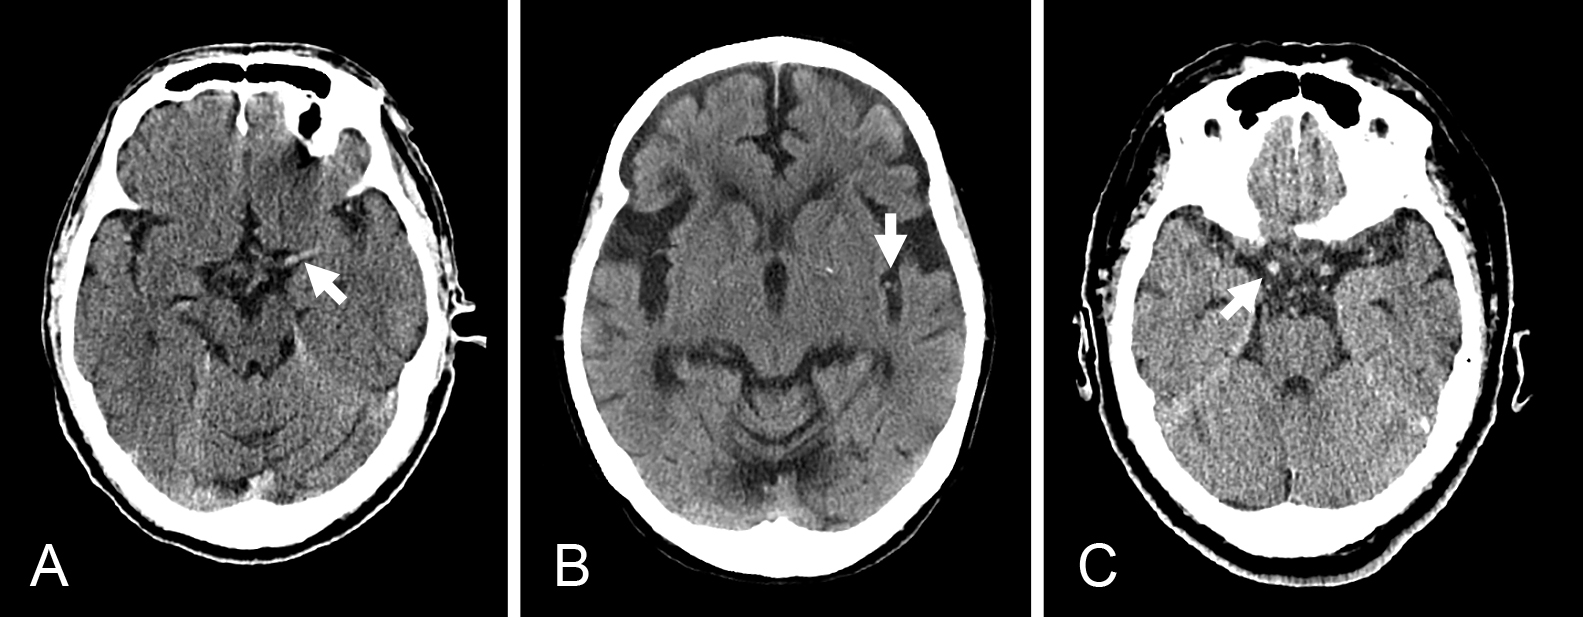

Claustrum signを呈したfebrile infection related epilepsy syndrome(FIRES)の55歳女性例

Febrile infection-related epilepsy syndrome (FIRES) with the claustrum sign in a 55-year-old woman: a case report

赤尾 剛, 市川 大, 藤盛 寿一, 中島 一郎

Go Akao, Dai Ichikawa, Juichi Fujimori, Ichiro Nakashima